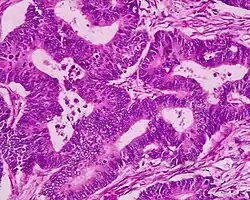

Adenomatous colon polyp with malignant focus at apex

Colorectal adenocarcinoma 100%

• In carcinoma in situ (Tis): cancer cells invading into the lamina propria, and may involve but not penetrate the muscularis mucosae. Can be classified as "high-grade dysplasia", because prognosis and management are essentially the same.[10]

• Invasive adenocarcinoma: Extending through the muscularis mucosae into the submucosa and beyond.[10]